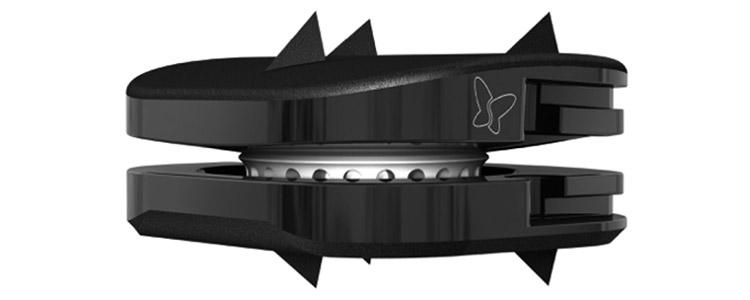

Resumen: Evaluamos los resultados clínicos y radiológicos con seguimiento mínimo de 2 años en pacientes intervenidos con prótesis de disco cervical. Se trata del primer estudio de prótesis de disco cervical en Uruguay con el único implante disponible en nuestro medio.